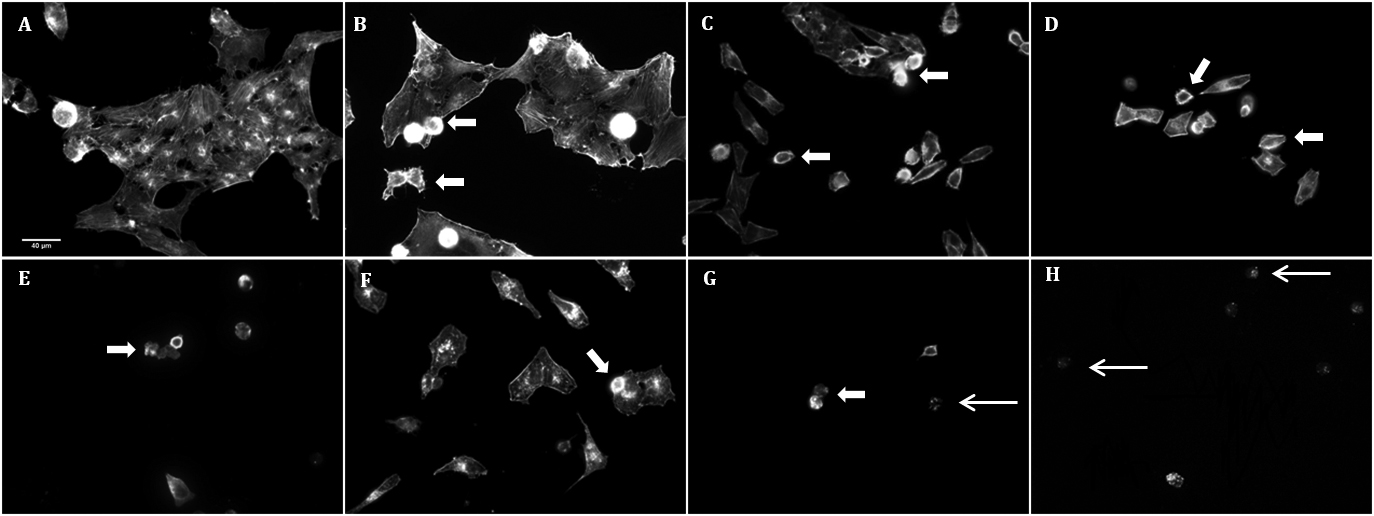

Figure 9. Phalloidin staining

(magnification 400×) showing the disorganization of F-actin

cytoskeleton in HO90 mM condition (B) compared to DMEM

control (A). BAK10−4%-stress (C),

BAK3.10−4% (D), and BAK5.10−4% (E)

induced cell blebs, cytoplasm shrinkage, and cell detachment in

a dose-dependent manner. All BAK concentrations induced more

disorganization and cell shrinkage than even the highest

hyperosmolar stress. Combinations of both stresses, namely HO90

mM+BAK10−4% (F), HO90 mM+BAK3.10−4%

(G), and HO90 mM+BAK5.10−4% (H) deeply

altered cell morphology, such as cytoplasm retraction associated

with cell-size decrease (large arrows), and induced a

dose-dependent cell death characterized by the presence of

apoptotic bodies (thin arrows).